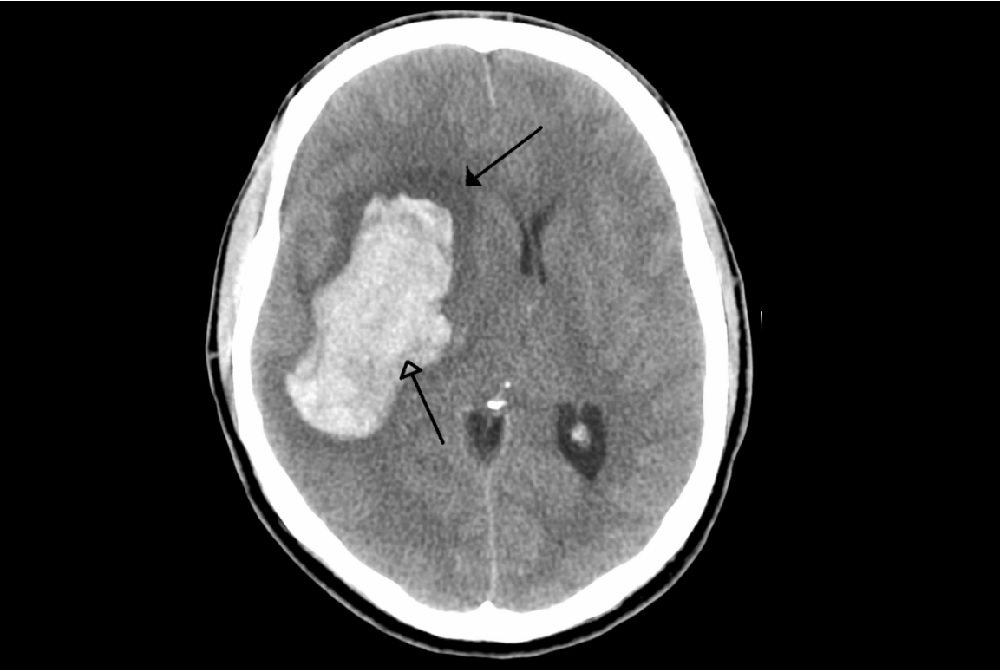

新華社周日(26日)報道,近日一個國際研究團隊通過對150多名中風患者長達半年的隨訪發現,患者出院後的前3個月是提升其與健康相關生活質量的關鍵期,應在此期間盡快啟動康復或支援項目以實現患者康復效果最大化。

研究發現,腦中風患者在出院後的生活質量變化受到年齡、性別、社會支持以及中風嚴重程度等多種因素影響。對於大部分患者而言,出院後的前3個月是康復和生活質量改善的關鍵期。對於病情較重、經濟困難或社會支持不足的患者,應在出院後3至6個月期間繼續加強康復訓練與支持,幫助他們盡可能提升生活質量。